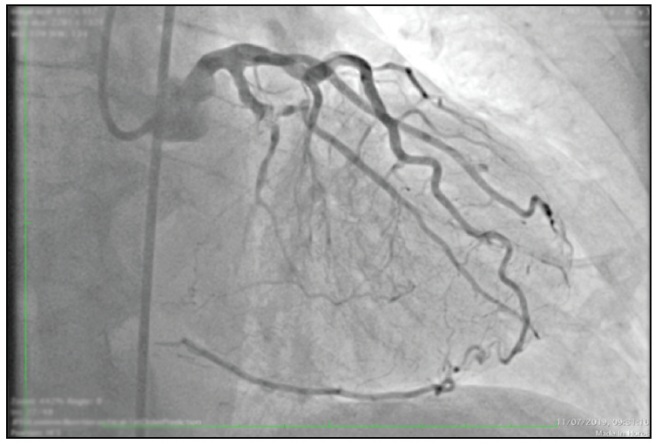

Cardiac Catheterisms, including Coronary Arteriography

Chronic total occlusion (put this picture) is defined as a complete obstruction of the coronary artery with a period of more than 3 months. It occurs in 18 to 54% of patients who undergo cardiac catheterizations. despite optimal medical management, 85% of patients remain symptomatic (Chest Pain, Shortness of breath, Tiredness, etc.) only 10% of these are taken to chronic total occlusion Percutaneous Coronary Intervention, taking into account that when has expertise, the success rate of the procedure is more than 90%, only 1 to 2% of interventional cardiologists in the United States have training in angioplasty of chronic total occlusions. This is why many of these patients are left under medical management.